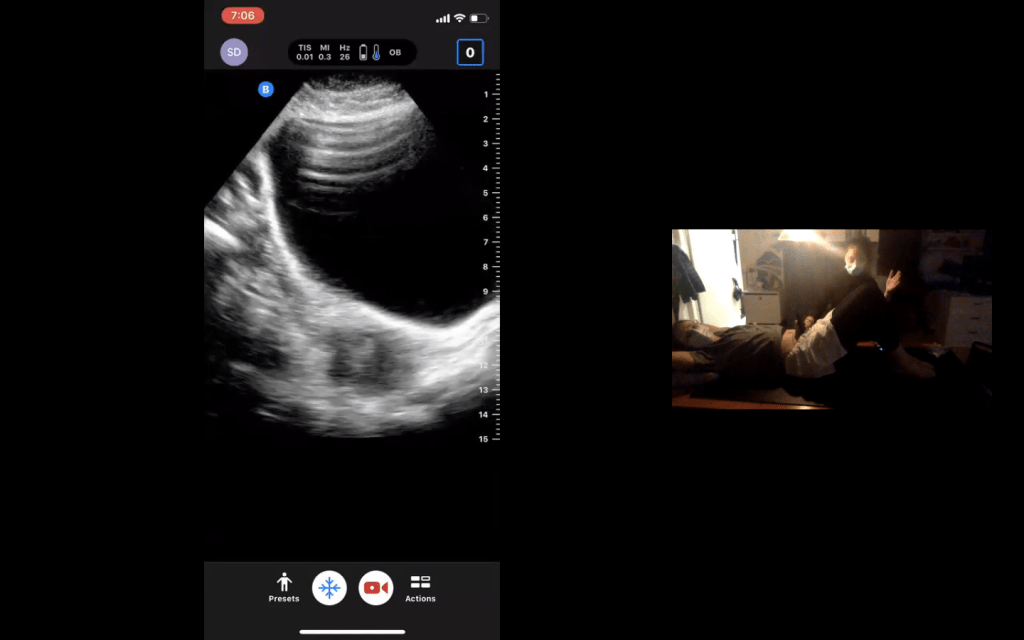

Here is a preview of our virtual session: